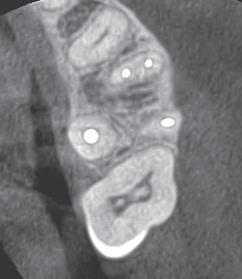

In February of 2024, a month after delivery of both prostheses, the patient reported for a denture adjustment

due to pain and discomfort. Upon evaluation, the patient had erosive lesions throughout her oral cavity including geographic tongue that were not consistent with pressure spots from her overdenture, as seen in figures 3-6.

FIGURE 3

FIGURE 4

FIGURE 5

FIGURE 6